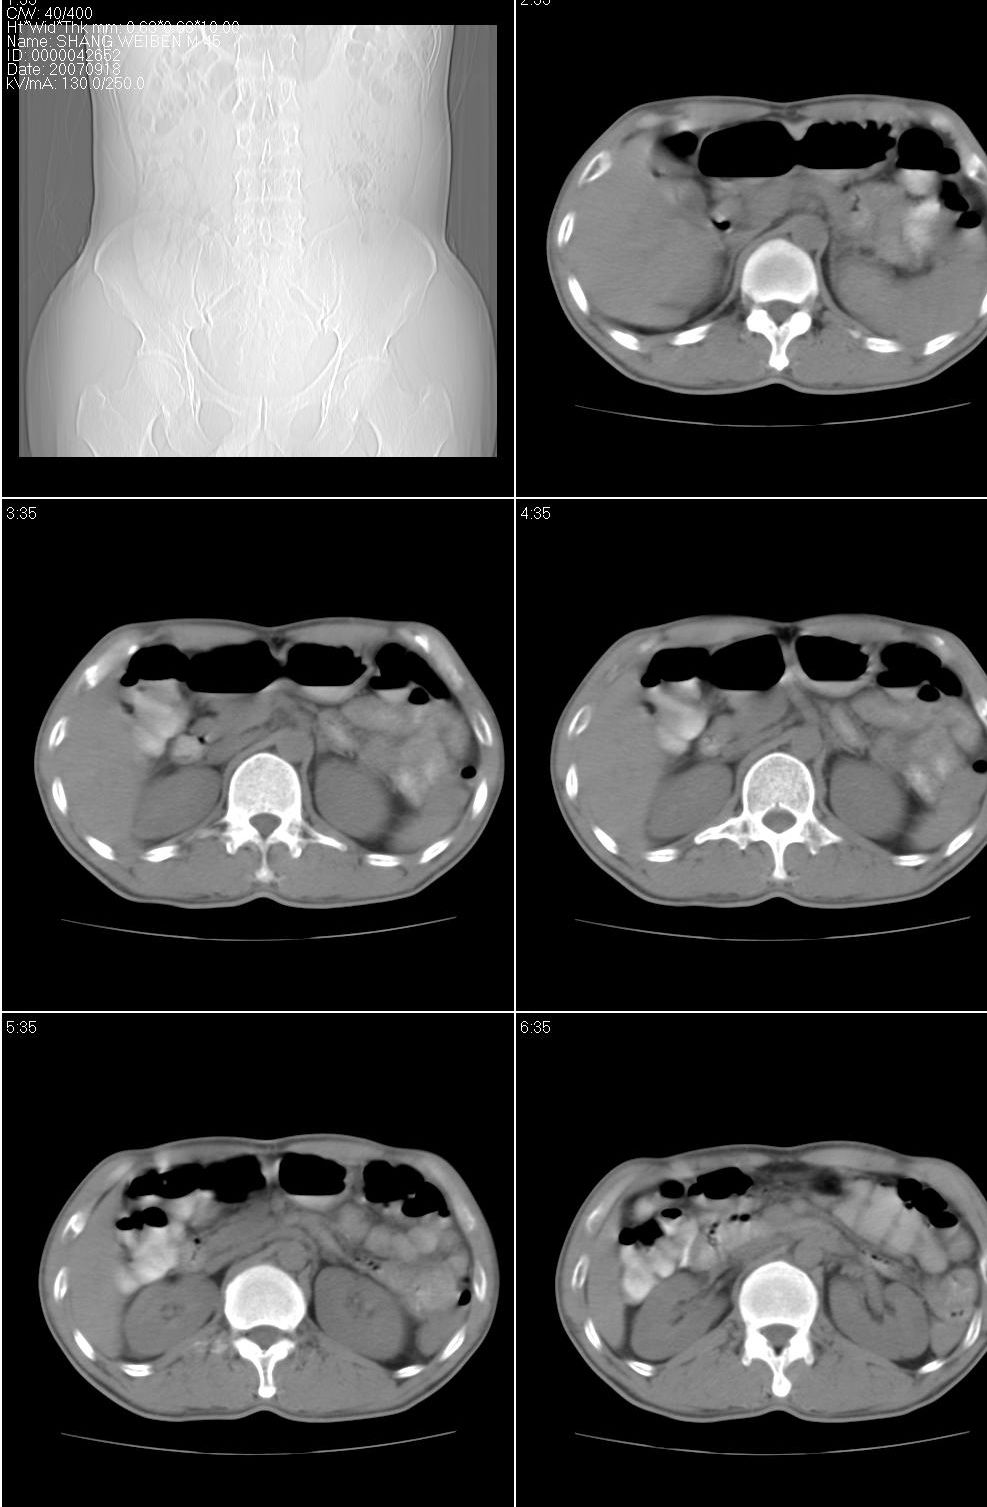

以下是引用jiangjing在2007-9-18 17:20:00的发言:[br]考虑生殖细胞肿瘤伴腹腔及腹膜后与腹股沟区淋巴转移,腹膜后大血管受压受侵

以下是引用老爱克斯新网客在2007-9-18 18:27:00的发言:[br]主动脉旁左侧腹股沟可见多发结节状病灶,1淋巴瘤,2转移瘤待除外,